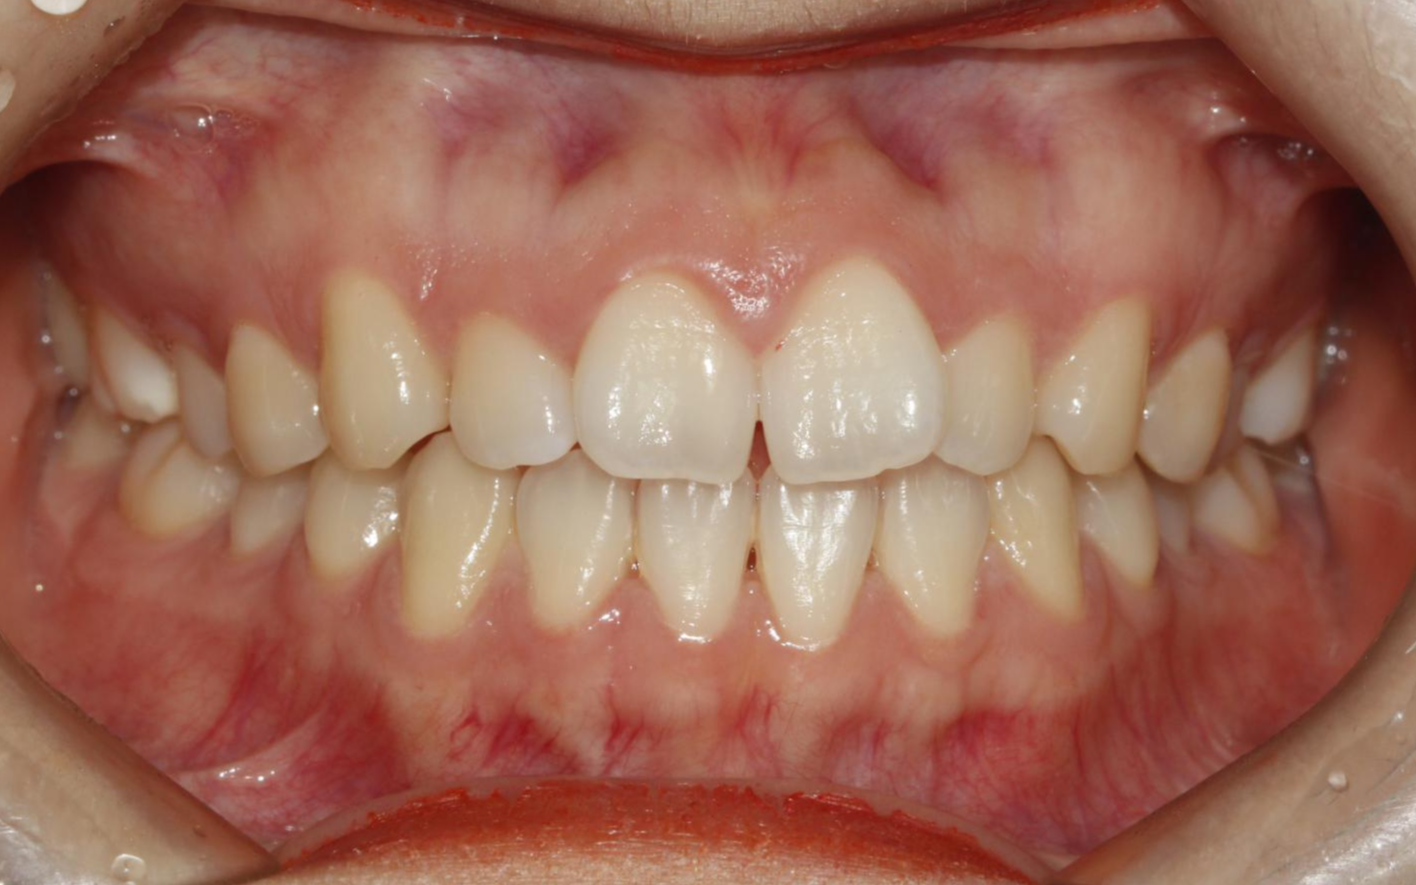

디테일한 치아 조절이 어렵다보니, 치아가 가지런하게 배열은 되지만, 가까이 들여다보면 치아배열이 조금 비뚤 수 있다.

만약 교정치료에 대한 기대감이 매우 높은 환자라면, 이런 부분에서 만족도가 떨어진다.

한 가지 아이러니한 상황이 생기는데, 투명교정은 부정교합이 심하지 않은 부분교정 환자에서 많이 사용하는데,

마지막에 이런 미세한 부분은 고치지 못하게 되니 불만족스러워하는 환자들이 꽤 발생한다.